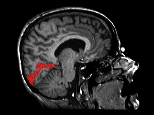

The following image indicates the location of the reconstructed surface (in red) in the brain.

Visual Cortex Reconstruction in a Sagittal MR Slice